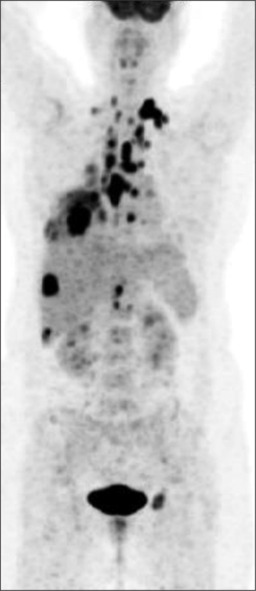

Lung cancer is the leading cause of cancer and cancer-related deaths, and India ranks the fourth highest country. Lung cancer is a highly aggressive malignancy with a tendency for rapid progression, making early detection and prompt treatment essential for improving patient outcomes. Lung cancer can spread locally into surrounding tissue as well as travel through lymphatics to other parts of the body, most often to bone, brain, liver, and adrenal glands. Metastasis to pituitary and pineal glands is extremely rare. The differential diagnosis for pituitary metastasis could be pituitary adenoma where lesion usually lies at the anterior aspect of pituitary fossa, whereas metastasis is seen at the posterior aspect. There is a paucity of published literature, with only a few cases reported of pituitary and pineal gland metastasis. Hence, to add to the literature, we present a case of pituitary metastasis in an older woman with lung cancer.